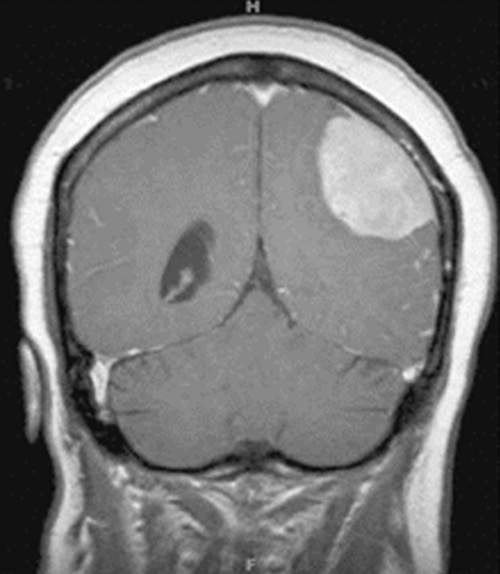

В данном случае это менингео

Менингеома